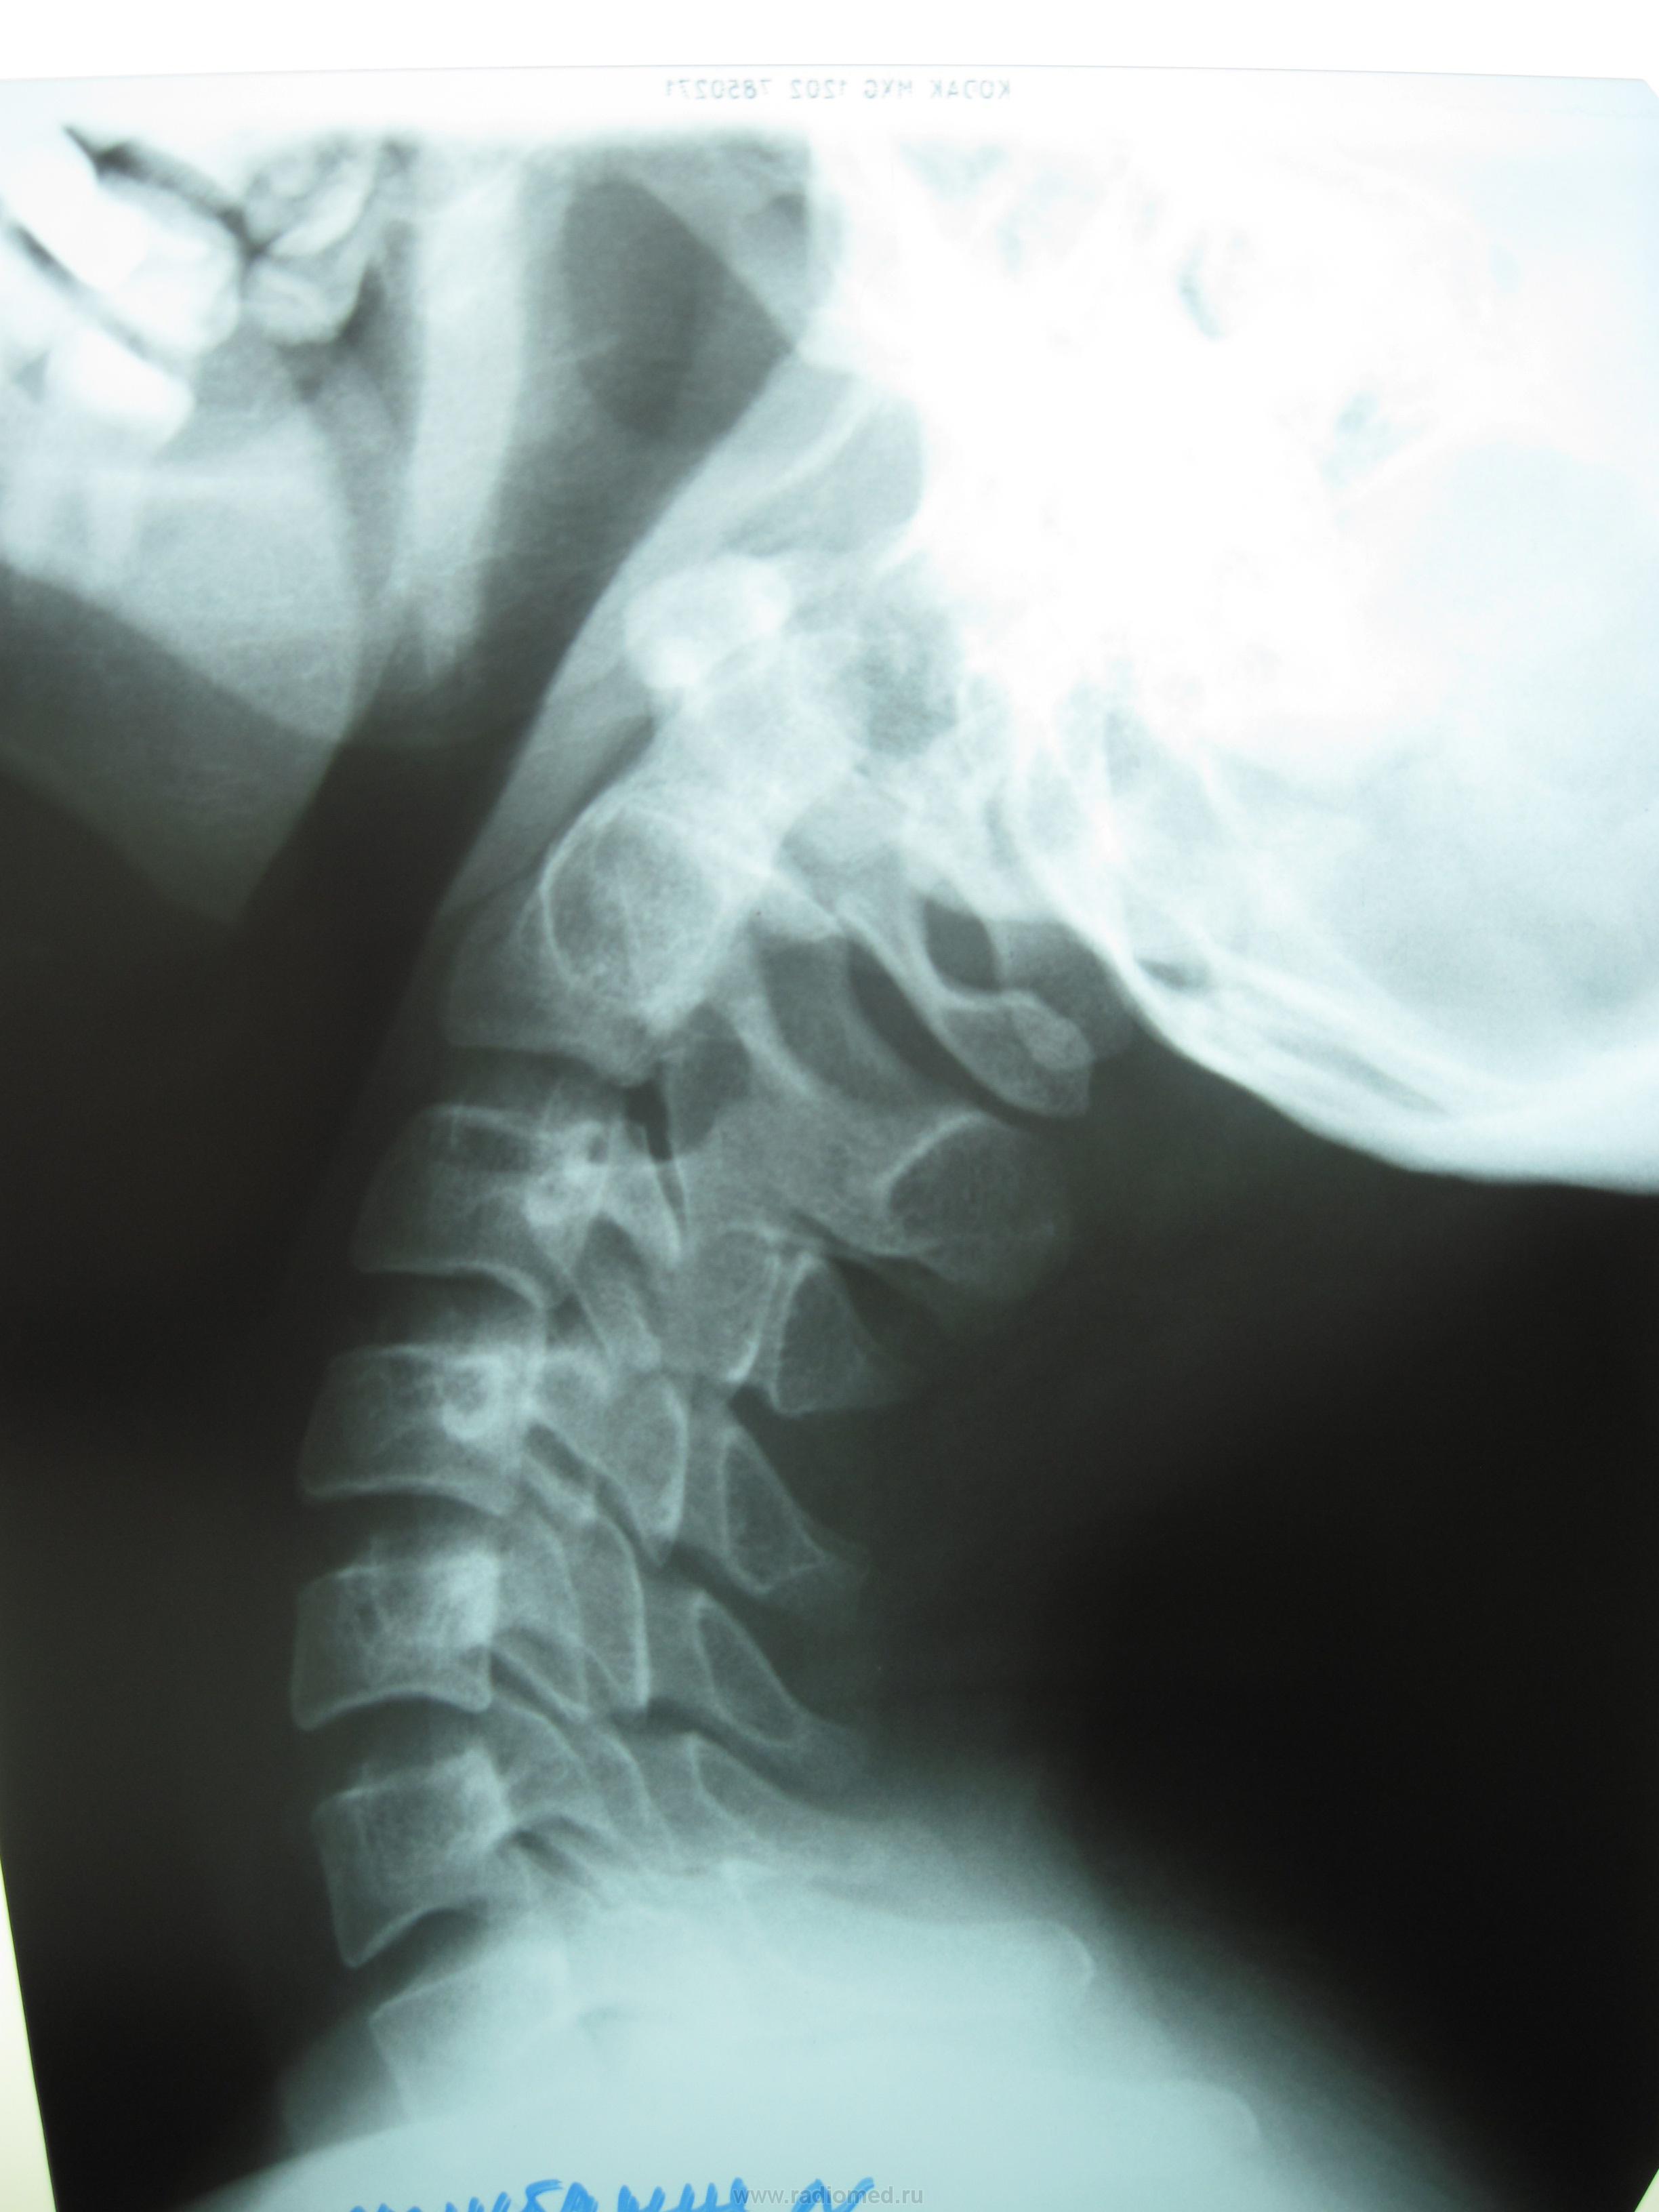

Помимо всего прочего, у первого пациента двольно редко встречающаяся аномалия/ вариант - расщепление (не зарастание) задней дуги С1 - очень интересно.

да, все верно. незаращение задней дужки первого шейного позвонка. самое интересное, оба случая встретились в один день! спасибо огромное за поддержку!

у пациентов - клиника остеохондроза. важное значение физиолигической нагрузки в данном случае обьясняется тем, что нередко незаращение задней дужки первого шейного позвонка сопровождается аномалей его соединения с затылочной костью, а именно - ассимиляцией или сращением! при этом клиника у пациентов появляется в 40-50 лет (- по старым источникам, в наши времена, видимо, уже и в 30-40 лет) в виде резких болей, как при обострении остеохондроза. обе пациентки попадают именно в этот возрастной интервал. так при сгибании и разгибании в шейном отделе, при сращении атланта с затылочной костью, расстояние между незаращенной дужкой и затылочной костью не менялось бы. в данных случаях - оно меняется, чем исключает данную патолгию.